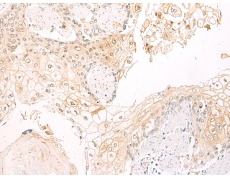

IHC positive control: |

Human esophagus cancer |